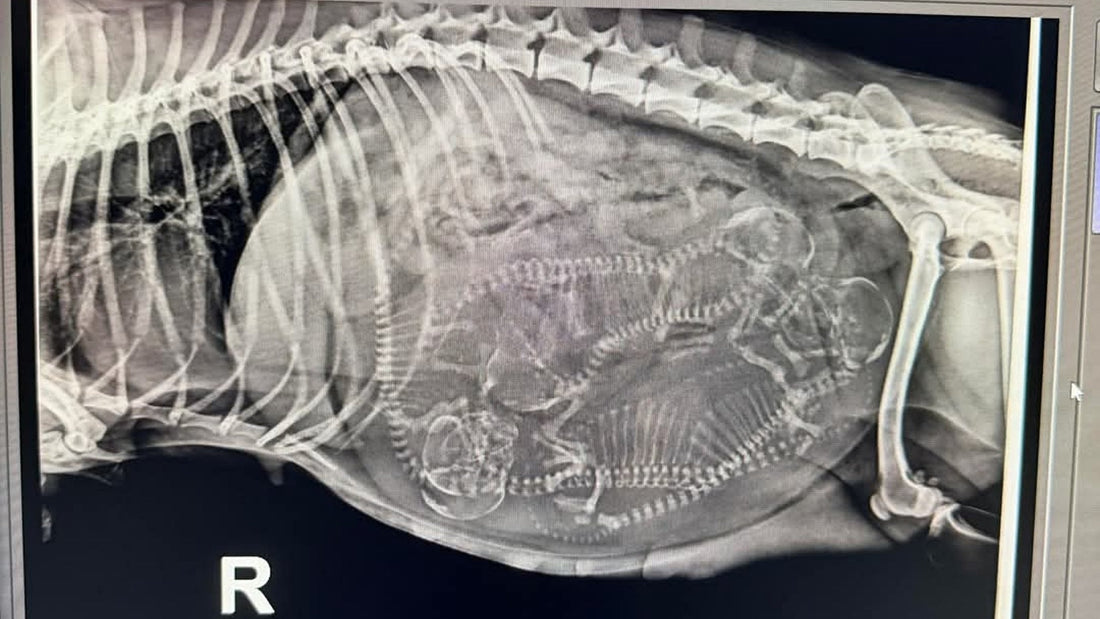

X-Ray in Canine Pregnancy

X-rays are generally performed after day 55, once puppy skeletons have mineralised.

What X-Ray Can Show

- Number of puppies

- Size and position of each puppy

- Skull and spine development

- Potential risk of difficult labour

X-ray is the most accurate way to determine how many puppies to expect at whelping.

We would like to thank Magnar Cavalier King Charles Spaniels for allowing us to use the depicted X-ray for our BLOG post and acknowledge the Cooinda Vet Hospital for taking the X-ray.